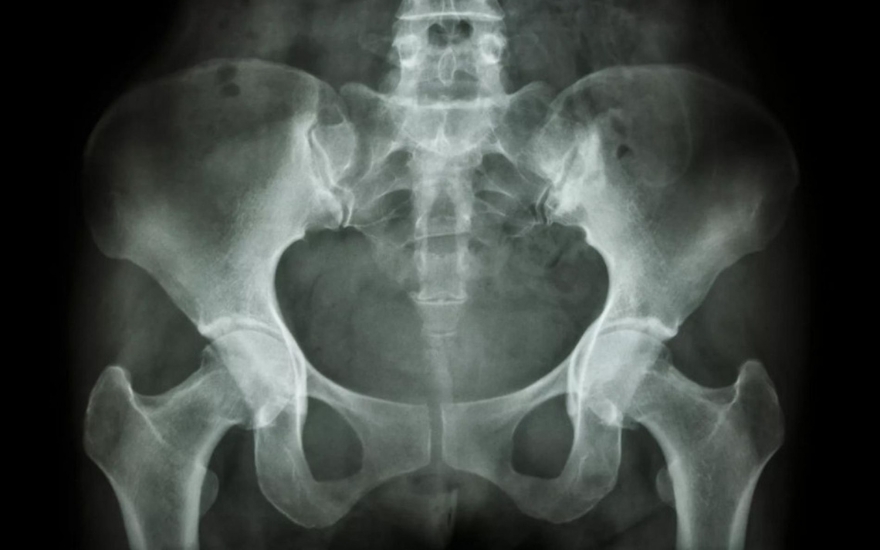

Khớp cùng chậu là phần nối liền giữa xương cùng cụt dưới cột sống thắt lưng và xương cánh chậu ở vùng hông. Tình trạng viêm tại một hoặc cả hai khớp cùng chậu được gọi là viêm khớp cùng chậu.

Vị trí khớp cùng chậu trên cơ thể.

Chụp X-quang và CT: Ở giai đoạn sớm, chụp X-quang chưa phát hiện được tổn thương khớp cùng chậu. Tuy nhiên, khi bệnh tiến triển nặng, chụp X-quang và CT có thể cho thấy tình trạng khe khớp cùng chậu rộng, xơ cứng trên bề mặt khớp, bào mòn khớp, dính một phần khớp cùng chậu... Giai đoạn 4: dính khớp cùng chậu hoàn toàn.

Hình ảnh viêm khớp cùng chậu trên phim chụp X-quang.